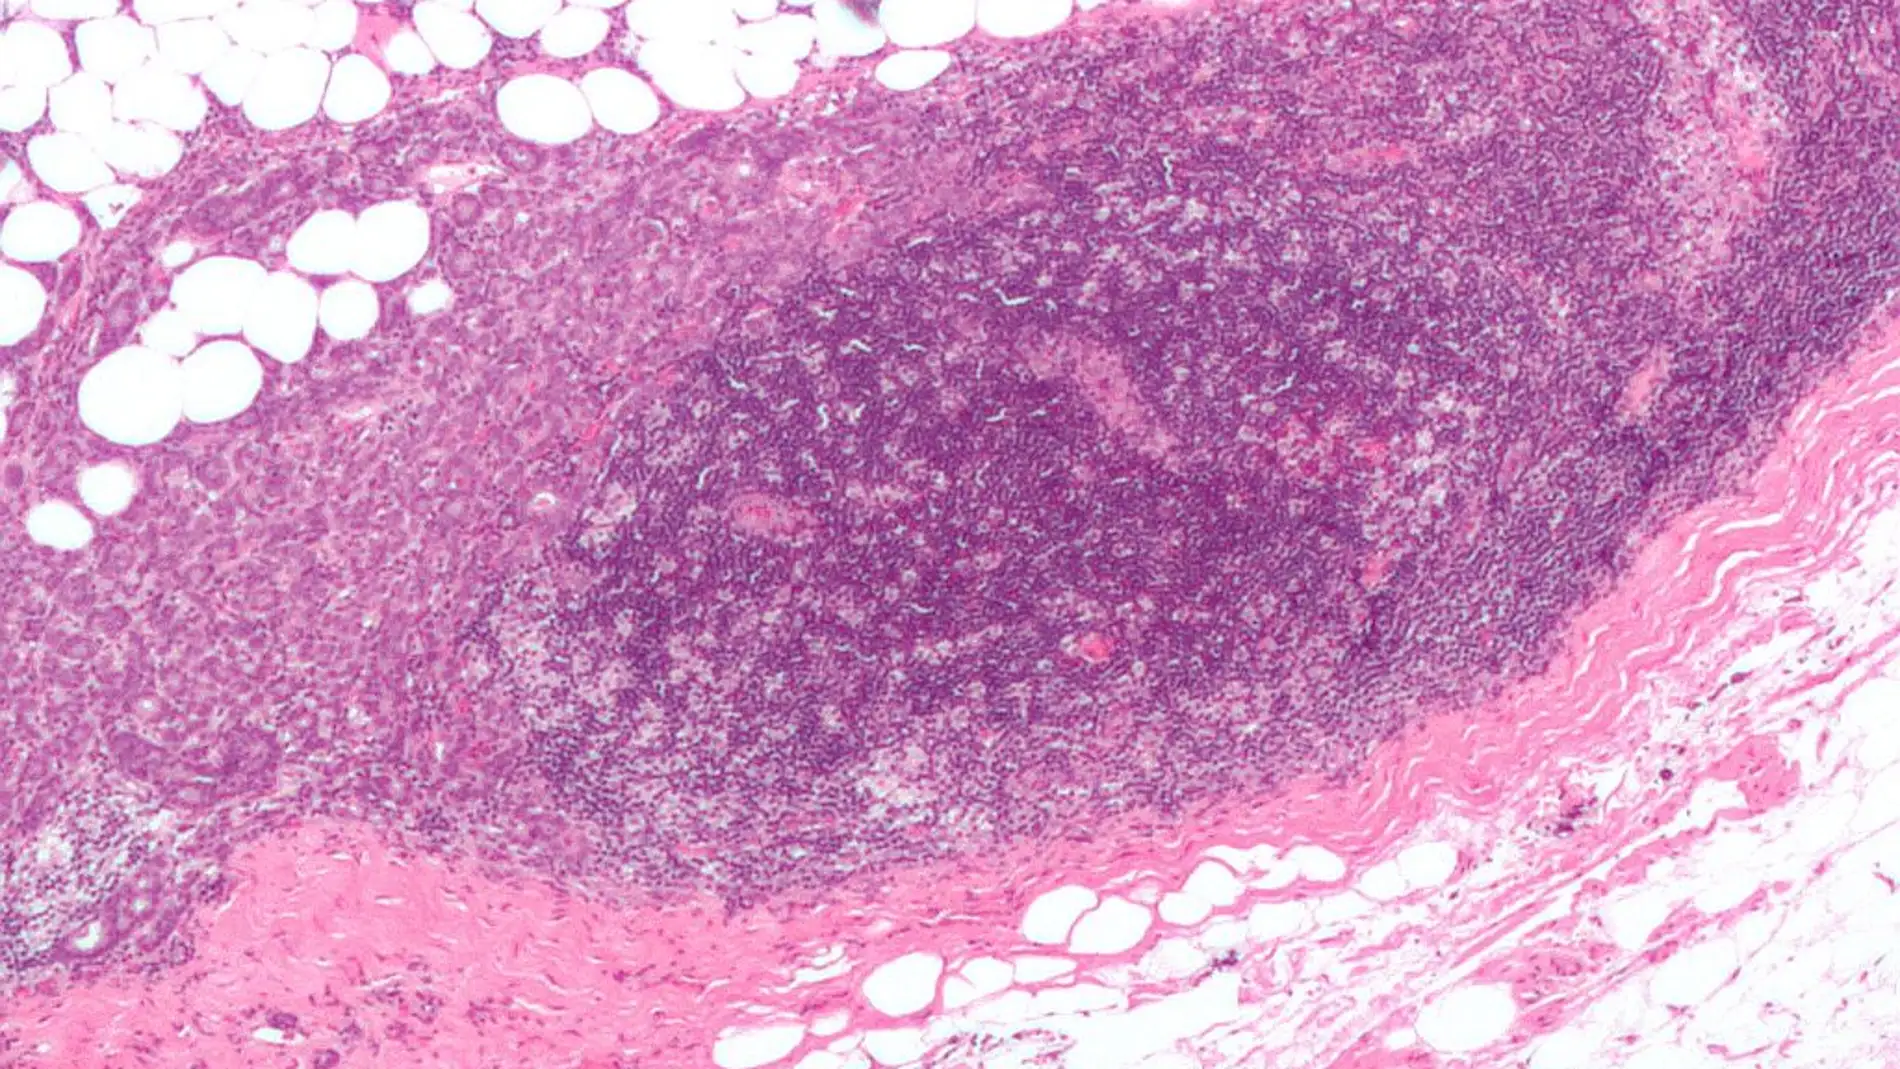

Un nuevo medicamento desarrollado por investigadores españoles funciona como un dron que identifica las células madre metastásicas, administra el fármaco y destruye únicamente estas células bloqueando la metástasis. Este nanofármaco ha sido ensayado en modelos animales de cáncer colorrectal con éxito y se podría utilizar en 20 tipos de tumores adicionales.

Investigadores del Centro de Investigación Biomédica en Red de Bioingeniería, Biomateriales y Nanomedicina (CIBER-BBN) en el Instituto de Investigación Biomédica de Sant Pau (IIB Sant Pau), la Universitat Autònoma de Barcelona (UAB) y el CSIC han demostrado la eficacia de un nanofármaco que elimina selectivamente las células madre metastásicas en modelos animales de cáncer de colon. Estos resultados han sido publicados en EMBO Molecular Medicine.

El equipo, liderado por Ramón Mangues, Antonio Villaverde y Esther Vázquez, ha demostrado que el fármaco actúa solamente sobre las células iniciadoras de metástasis a través de su interacción específica entre un péptido presente en la nanopartícula proteica que lo transporta y el receptor celular CXCR4 que se encuentra sobreexpresado en las células tumorales.

Esto permite atacar solamente a las células tumorales, bloqueando su diseminación en estadios tempranos, de manera que previene la aparición de metástasis a la vez que evita los efectos adversos derivados de los tratamientos habituales.